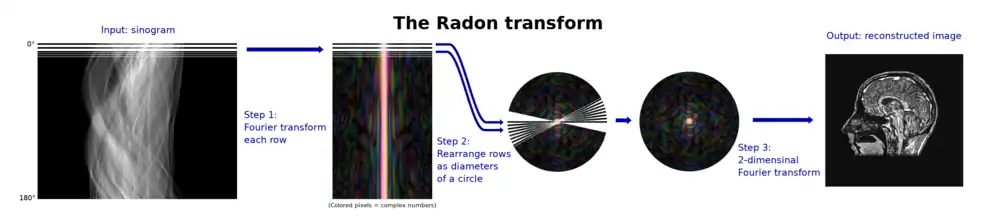

Relationship with the Fourier transform

The Radon transform is closely related to the Fourier transform. We define the univariate Fourier transform here as: For a function of a -vector , the univariate Fourier transform is: For convenience, denote . The Fourier slice theorem then states: where

Thus the two-dimensional Fourier transform of the initial function along a line at the inclination angle is the one variable Fourier transform of the Radon transform (acquired at angle ) of that function. This fact can be used to compute both the Radon transform and its inverse. The result can be generalized into n dimensions:

Explicit and computationally efficient inversion formulas for the Radon transform and its dual are available. The Radon transform in dimensions can be inverted by the formula:[11] where , and the power of the Laplacian is defined as a pseudo-differential operator if necessary by the Fourier transform: For computational purposes, the power of the Laplacian is commuted with the dual transform to give:[12] where is the Hilbert transform with respect to the s variable. In two dimensions, the operator appears in image processing as a ramp filter.[13] One can prove directly from the Fourier slice theorem and change of variables for integration that for a compactly supported continuous function of two variables: Thus in an image processing context the original image can be recovered from the 'sinogram' data by applying a ramp filter (in the variable) and then back-projecting. As the filtering step can be performed efficiently (for example using digital signal processing techniques) and the back projection step is simply an accumulation of values in the pixels of the image, this results in a highly efficient, and hence widely used, algorithm.